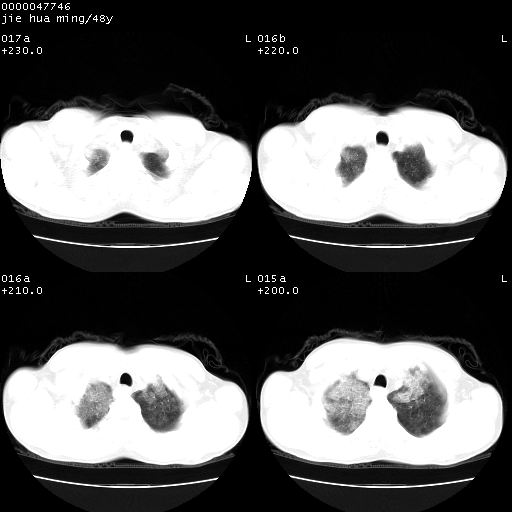

以下是引用hhcckk在2008-5-1 8:06:00的发言:[br]支持肺泡蛋白沉积症[br]依据:[br]1、病灶边缘清楚----地图征[br]2、病灶内部小叶间隔或小叶内间隔增厚所形成的网格状影----碎石路样表现[br]3、抗炎治疗无效(炎症抗炎治疗有效)[br]4、纵隔内未见肿大淋巴结(肺泡细胞癌时常有)[br][br]附肺泡蛋白沉积症资料[br][br]肺泡蛋白沉积症(pulmonary alveolar proteinosis)是一种原因不明的以肺泡腔内大量含脂糖蛋白样物质沉积为特征的疾病。[br]病理改变:(1)肺泡和细支气管腔内充满大量含脂糖蛋白样的粘稠物质,该物质为颗粒状或絮状的糖原pas染色阳性的磷脂蛋白。(2)肺泡壁及其间隔无异常改变。胸膜和淋巴结不受累及。(3)晚期可出现弥漫性肺间质纤维化。[br]临床表现:(1)好发年龄30~50岁,男性多于女性,偶见于儿童;(2)主要症状为呼吸困难、咳嗽、低热、消瘦、低氧血症和杵状指等。1/3的患者无症状。(3)实验室检查:痰液或肺泡灌洗液中可找到pas染色阳性颗粒物质。[br]hrct表现:肺泡蛋白沉积症具有特征性改变,即“碎石路样”表现(crazy-paving appearance,cpa)。主要包括(1)斑片状磨玻璃影:指肺野密度朦胧增加,内可见肺血管纹理影,系肺泡腔内充满低密度的磷脂蛋白物质所致。(2)其内部小叶间隔或小叶内间隔增厚所形成的网格状影,为小叶间隔水肿、肺泡壁内淋巴细胞和巨噬细胞浸润以及小叶内淋巴管扩张的缘故。(3)病灶边缘清楚,呈地图样分布于肺野外围或肺门及中央区。[br]

以下是引用zsl6918在2008-5-1 7:35:00的发言:[br]双肺磨玻璃样病变,可见铺碎路石征,病变区与正常区交错。边界清晰。符合肺泡蛋白质沉着征,高分辨扫描会更清楚漂亮。建议临床肺泡灌洗。

以下是引用yangyudong333在2008-5-1 5:36:00的发言:[br][br] 两肺广泛毛玻璃样的片状影,密度不均,边缘欠清,呈碎石路样改变,[br]考虑,1双肺间质性肺炎,2肺泡蛋白沉积症[br]